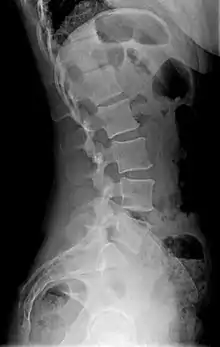

X-ray of lumbar hyperlordosis

Measurement and diagnosis of lumbar hyperlordosis can be difficult. Obliteration of vertebral end-plate landmarks by interbody fusion may make the traditional measurement of segmental lumbar lordosis more difficult. Because the L4–L5 and L5–S1 levels are most commonly involved in fusion procedures or arthrodesis and contribute to normal lumbar lordosis, it is helpful to identify a reproducible and accurate means of measuring segmental lordosis at these levels.[16][17] A visible sign of hyperlordosis is an abnormally large arch of the lower back and the person appears to be puffing out his or her stomach and buttocks.

Precise diagnosis is done by looking at a complete medical history, physical examination, and other tests of the patient. X-rays are used to measure the lumbar curvature. On a lateral X-ray, a normal range of the lordotic curvature of between 20° and 60° has been proposed by Stagnara et al., as measured from the inferior endplate of T12 to the inferior endplate of L5.[18] The Scoliosis Research Society has proposed a range of 40° and 60° as measured between the upper endplate of Th12 and the upper endplate of S1.[18] Individual studies, although using other reference points, have found normal ranges up to approximately 85°.[18] It is generally more pronounced in females.[18] It is relatively constant through adolescence and young adulthood, but decreases in the elderly.[18]